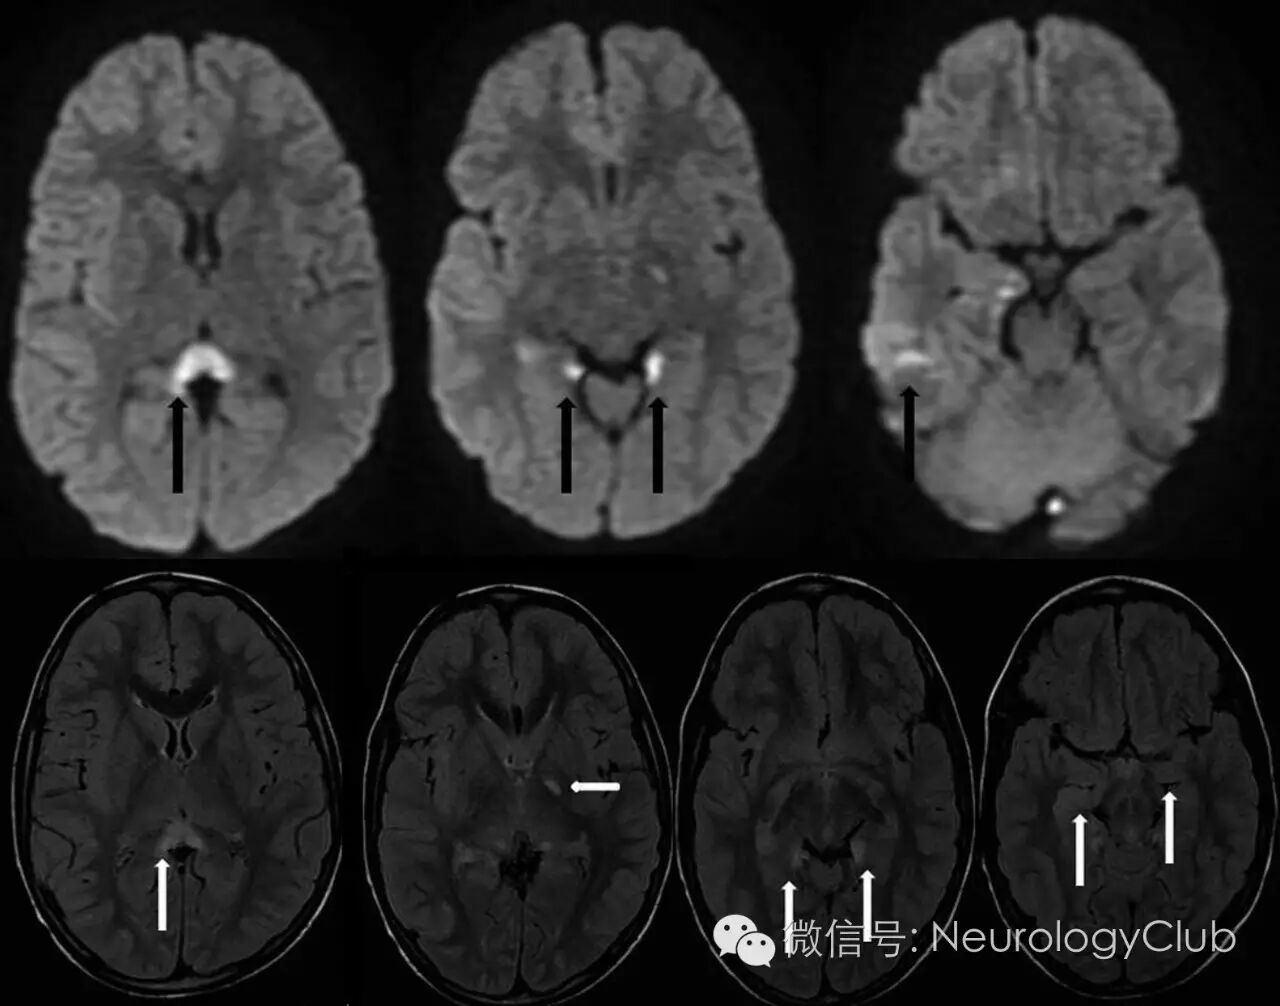

(图6:钩端螺旋体感染相关的RESLES。A:FLAIR;B-C:T2WI;可见半月形SCC高信号病灶,称“小回旋镖征

(图7:钩端螺旋体感染相关的RESLES。A:FLAIR;B-C:T2WI;4周后复查,病灶消失

(图8:立克次体感染相关的RESLES。上:DWI;下:FLAIR;可见SCC“回旋镖征”以及其他部位病灶;10天后复查异常信号消失

(图9:立克次体感染相关的RESLES。A:DWI;B:ADC;C:T1增强;可见SCC回旋镖征”及胼胝体膝部病灶)

磁共振是诊断RESLES的首选检查。其特征性的影像学表现为SCC(一般位于中心区域)局限性的椭圆形或条状的病变,如出现整个胼胝体压部受累的条状病变,称为“回旋镖征”(Boomerang sign)。病灶于T1WI上呈等或低信号,T2WI/FLAIR和DWI上均为高信号,ADC值降低,增强扫描无明显强化。目前尚无胼胝体压部发生囊病或坏死的报道。病变可不仅仅局限在胼胝体压部,其他部位如膝部、体部也可同时出现,甚至可以累及胼胝体外,如脑室旁白质,皮质下白质和基底节区,而这些病灶基本上也是可逆的。最近的研究表明,胼胝体外病变的出现往往提示预后不良,而胼胝体其他部位是否出现病灶与预后并无明显联系。各种病因导致的RESLES影像学异常和消失的时间如表1所示。